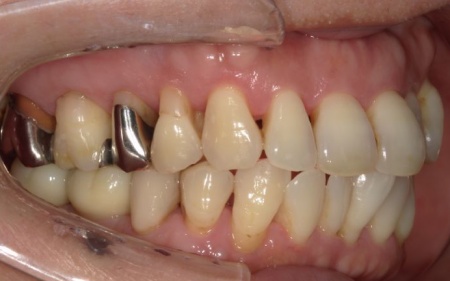

拝見したところ、左上の抜歯部周辺は歯を支える骨が溶ける「骨吸収」が進行し、隣接している歯を含めた複数の歯がひどくグラグラしており、温存が困難です。

また、右下奥歯には、両隣の歯を土台にして橋を渡すように欠損部を補う被せ物「ブリッジ」が装着されていました。

右下奥歯は2本欠損しており、親知らず(第3大臼歯)と手前の奥歯(第2小臼歯)の2本でブリッジを支えていますが、これは親知らずに過度な負荷がかかる構造です。

親知らずはすでに大きく傾いており、こちらも温存が難しいため、ブリッジを除去してから親知らずを抜く必要があります。

また、右下の手前にある奥歯2本(第1小臼歯、第2小臼歯)は、新しく詰め物を作製して噛み合わせと見た目を整えています。